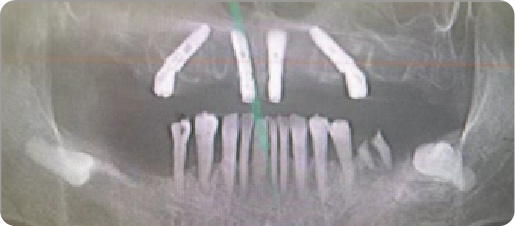

Multiple Dental Implants Case

BEFORE

VS

AFTER

Name:Mr QinAge:34

Evaluation: Missing two or three maxillary anterior teeth.

Treatment Plan:Three implants were placed to anchor a bridge that replaces five teeth,with two artificial teeth suspended in between.

Patient Feedback:Experience a secure, long-lasting solution that protects your healthy teeth,feels comfortable, and looks bcautifully natural.

For Prevention:Consistent care, including diligent oral hygiene and regular professional maintenance,is essential for the long-term durability of dental implants.